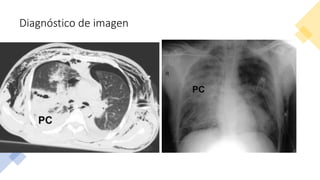

Diagnóstico de imagen

• Infradiagnóstico Rx

• ~ 1000 pacientes; TAC –

100% contusiones

pulmonares vs 38% Rx.*

• Diagnóstico temprano

 volumen total

contusion.

Diagnóstico de imagen •Infradiagnóstico Rx • ~ 1000 pacientes; TAC – 100% contusiones pulmonares vs 38% Rx.* • Diagnóstico temprano  volumen total contusion.